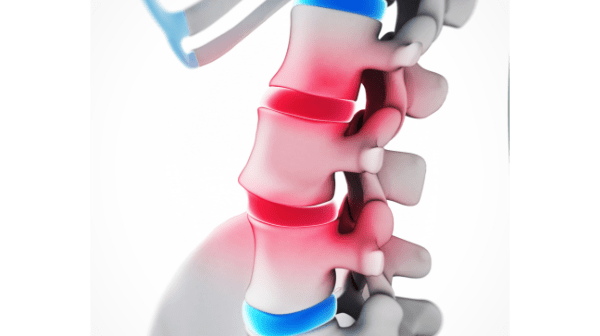

척추전방전위증

척추전방전위증은 선천적인 관절돌기의 손상이나, 외부 충격에 의한 손상, 혹은 척추의 퇴행에 의해

상하척추

연결부가 늘어나는 등의 여러 요인으로 인해 위 척추 뼈가 아래 척추 뼈보다 앞으로 밀려나며 통증이

발생하는 질환입니다.

비정상

척추전방전위증 환자 중엔 외상 등으로 관절 돌기가 손상되어 척추가 분리되는 척추분리증이 있는 경우가

많습니다. 척추분리증은 특별한 통증이나 증상이 없어 방치해두기 쉬운데, 허리를 무리하게 사용하거나 운동

혹은 근육과 안대의 약화 등으로 전방전위증으로 전이되면 요통 및 좌골신경통이 발생할 뿐만 아니라

척추관협착증이나 허리디스크(요추추간판탈출증), 퇴행성디스크 등을 유발하기도 합니다.